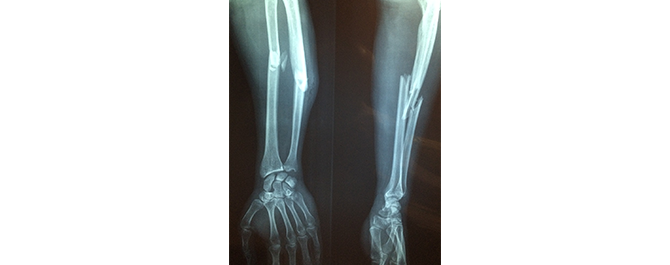

De tyska forskarna hänvisar till flera undersökningar som har visat att typ 1-diabetiker har en försämrad bentäthet vilket gör skelettet skört och att läkningsprocessen tar längre tid. Långvariga höga blodsocker försämrar bentätheten.

De påpekar också att frakturrisken är högre bland typ 1- än bland typ 2-diabetiker. Till exempel är höftfrakturer fem gånger vanligare bland typ 1-diabetiker.